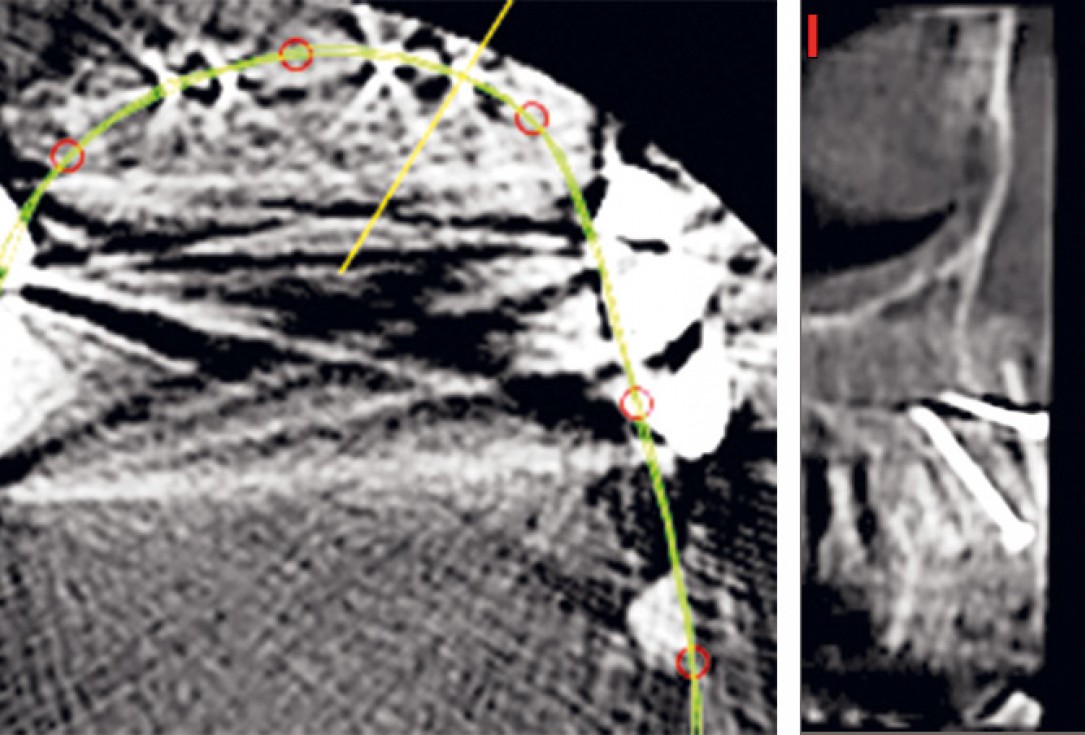

03 / 22 - Initial situation – CBCT image of the first quadrant

Three-dimensional augmentation with maxgraft® cortico - M.Sc. E. Kapogianni